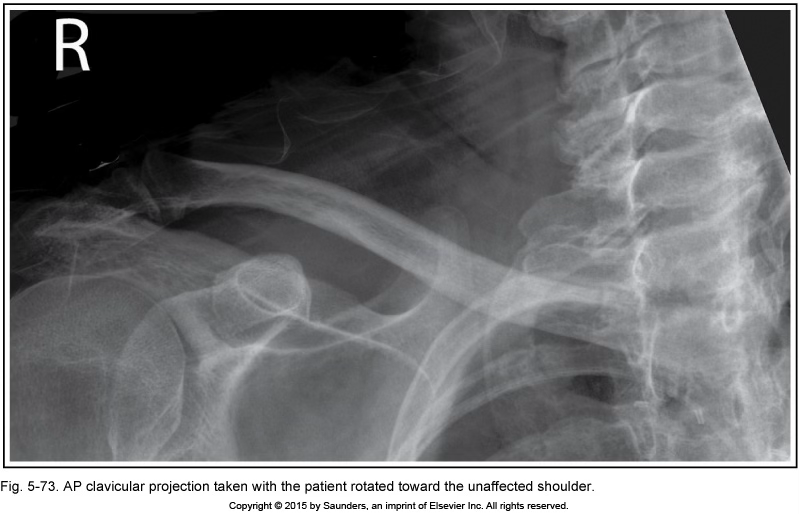

AP clavicle

Pt rotated into LPO (unaffected shoulder)

(medial end of clavicle is superimposing vertebral column)